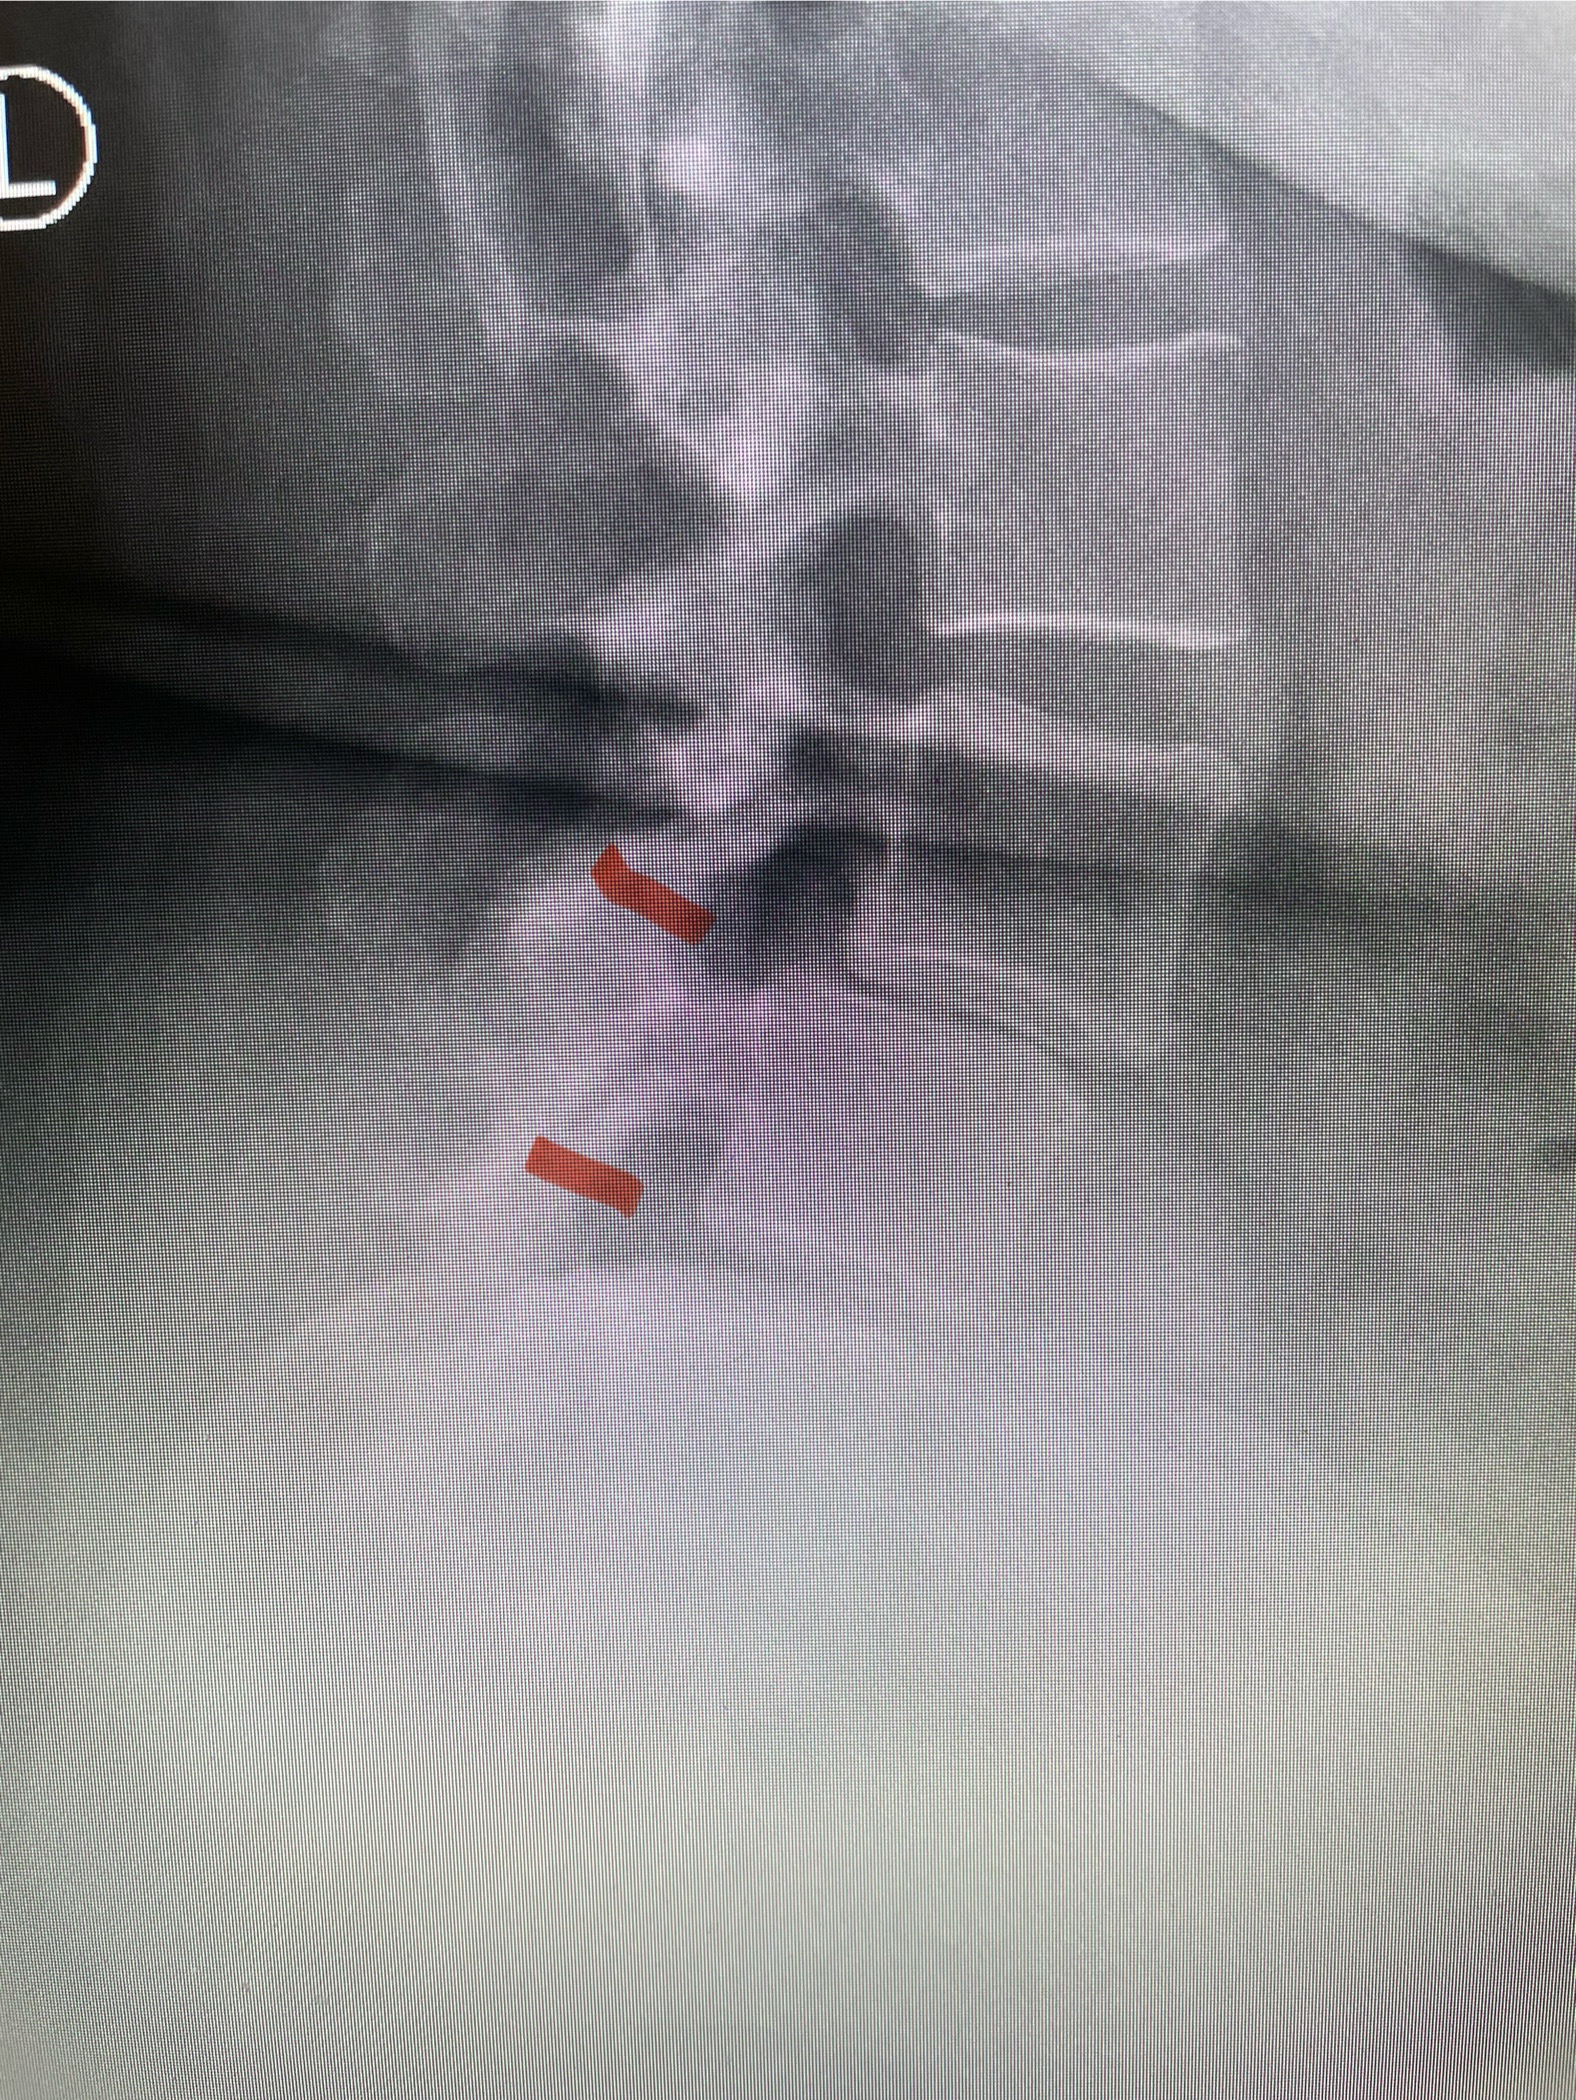

In patients who have lumbar spinal stenosis and significant cardio/pulmonary conditions, surgery is the last resort. However, some patients with these conditions may fail all means of conservative management where surgery becomes their only option for relief. In those patients, one should strive to do the least complex surgery that is necessary to get the job done for them. In this case study, we are confronted with a new problem in a 78 year-old male patient that was in poor medical condition who had had two prior lumbar laminectomies with resultant fusion and instrumentation from L4-S1. There was now retrolisthesis of L2-3 with severe stenosis (Fig.1)

Fig 1a: Sagittal T2 weighted lumbar MRI demonstrating severe L2-3 stenosis (red arrow)